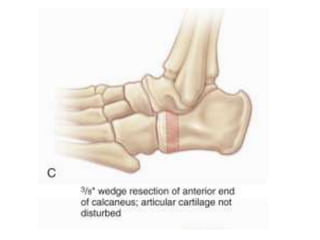

Dilwyn Evans Osteotomy

• Posteromedial release

• Calcaneocuboid wedge resection and arthrodesis

• Shortens lateral column

• Stiffness at subtalar and midfoot joints

• Preferred in older children (4-8 yrs)

• standard technique for recurrent clubfoot deformity